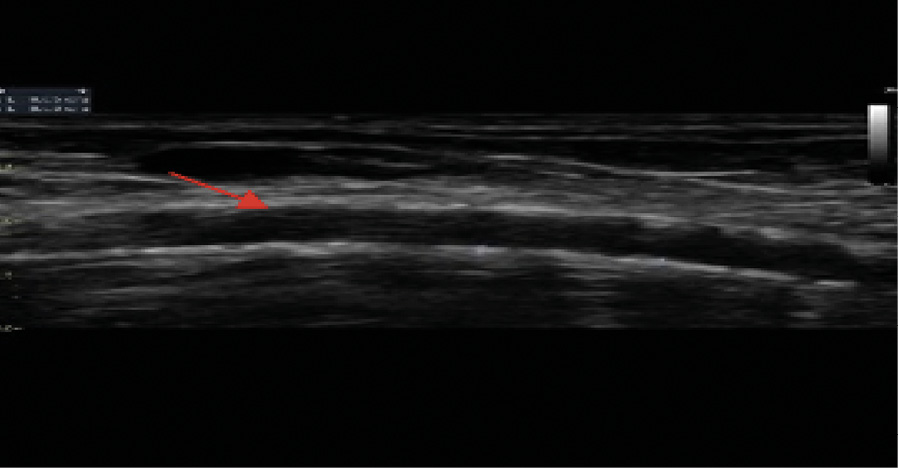

При ультразвуковом дуплексном сканировании артерий нижних конечностей в 2022 г. выявлен атеросклероз магистральных артерий нижних конечностей, эхографические признаки выраженного кальциноза магистральных артерий (рис. 4), окклюзирующий хронический тромбоз левой задней большеберцовой артерии в верхней и средней трети голени.

Рис. 4. Эхограмма пациента Т. Левая передняя большеберцовая артерия. Визуализируется диффузное относительно равномерное повышение эхогенности сосудистой стенки в сочетании с утратой дифференцировки на слои на всем протяжении (красная стрелка). Эхографические тени от повышенного содержания солей кальция фрагментарно перекрывают просвет и нижнюю стенку сосуда (желтые стрелки)

При измерении лодыжечно-плечевого индекса (ЛПИ) доплеровский сигнал не исчезал даже в случае нагнетания давления в манжете более 300 мм рт. ст. по трем измеряемым артериям. По левой окклюзированной в проксимальном сегменте задней большеберцовой артерии получен показатель 1,3, что отражает значимую кальцификацию сосудистой стенки. Распространение кальциноза наблюдалось и на пальцевые артерии, что сопровождалось несжимаемостью этих артерий, свойственной пациентам с ХБП, получающим заместительную почечную терапию, или пациентам после трансплантации почки. По данным ультразвукового дуплексного сканирования внечерепных отделов брахиоцефальных артерий, в устье левой внутренней сонной артерии выявлена кальцинированная атеросклеротическая бляшка (стеноз 20%). Ультразвуковое дуплексное сканирование артериовенозной фистулы левой верхней конечности: эхографические признаки кальциноза (рис. 5) с симптомами ускоренного кровотока в бассейне левой плечевой артерии (230 см/с) в сравнении с контрлатеральной плечевой артерией (77 см/с). Избыточное шунтирование артериальной крови по фистуле напрямую в венозное русло, предположительно, может способствовать развитию ригидности сосудистой стенки, что обусловлено изменением кинетических характеристик движущейся крови (давления, объема, скорости), иными словами, «напряжением сдвига». Вследствие повышенного воздействия на механорецепторы эндотелия могут активироваться патологические процессы, направленные на активацию сосудистой кальцификации у нашего пациента.